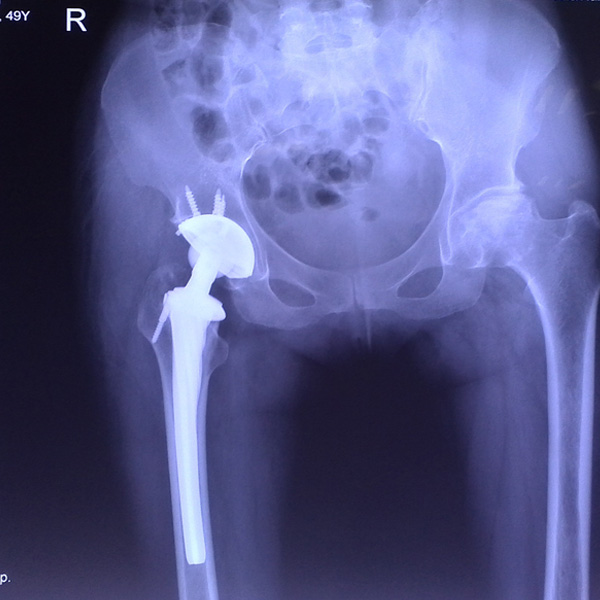

• 右側全髖關節置換右側全髖關節置換手術后手術前

右側全髖關節置換

患者姜某某,女50歲,診斷為“股骨頭壞死”,右側髖關節疼痛到不能生活自理。經平臺推薦到哈爾濱醫科大學附屬第二醫院骨關節科就診,患者想......